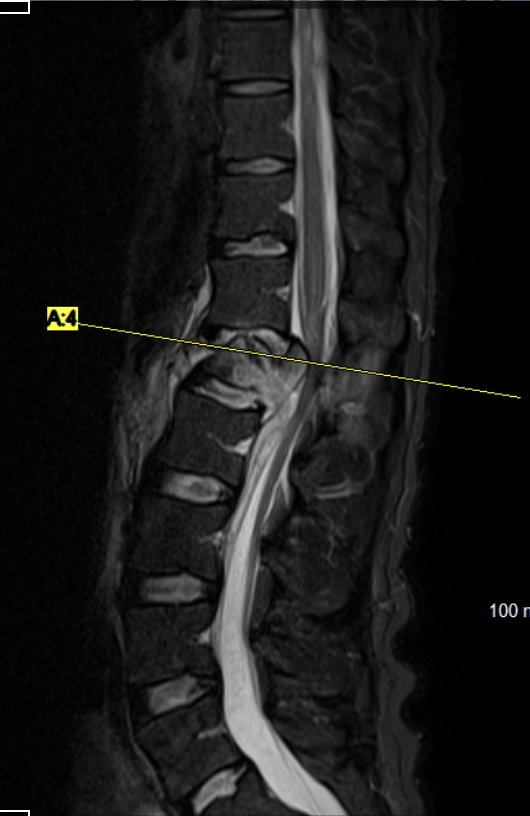

Rachis Dégénératif

Je prends également en charge les affections dégénératives du rachis cervical et lombaire, telles que la hernie discale, la sciatique, la sténose spinale ou la myélopathie cervicale.

En fonction de chaque patient,  la technique est adaptée pour la cure de hernie discale, la laminectomie, la laminoplastie ou la chirurgie cervicale antérieure (type ACDF), en privilégiant toujours les approches mini-invasives et endoscopiques pour une récupération rapide et durable.